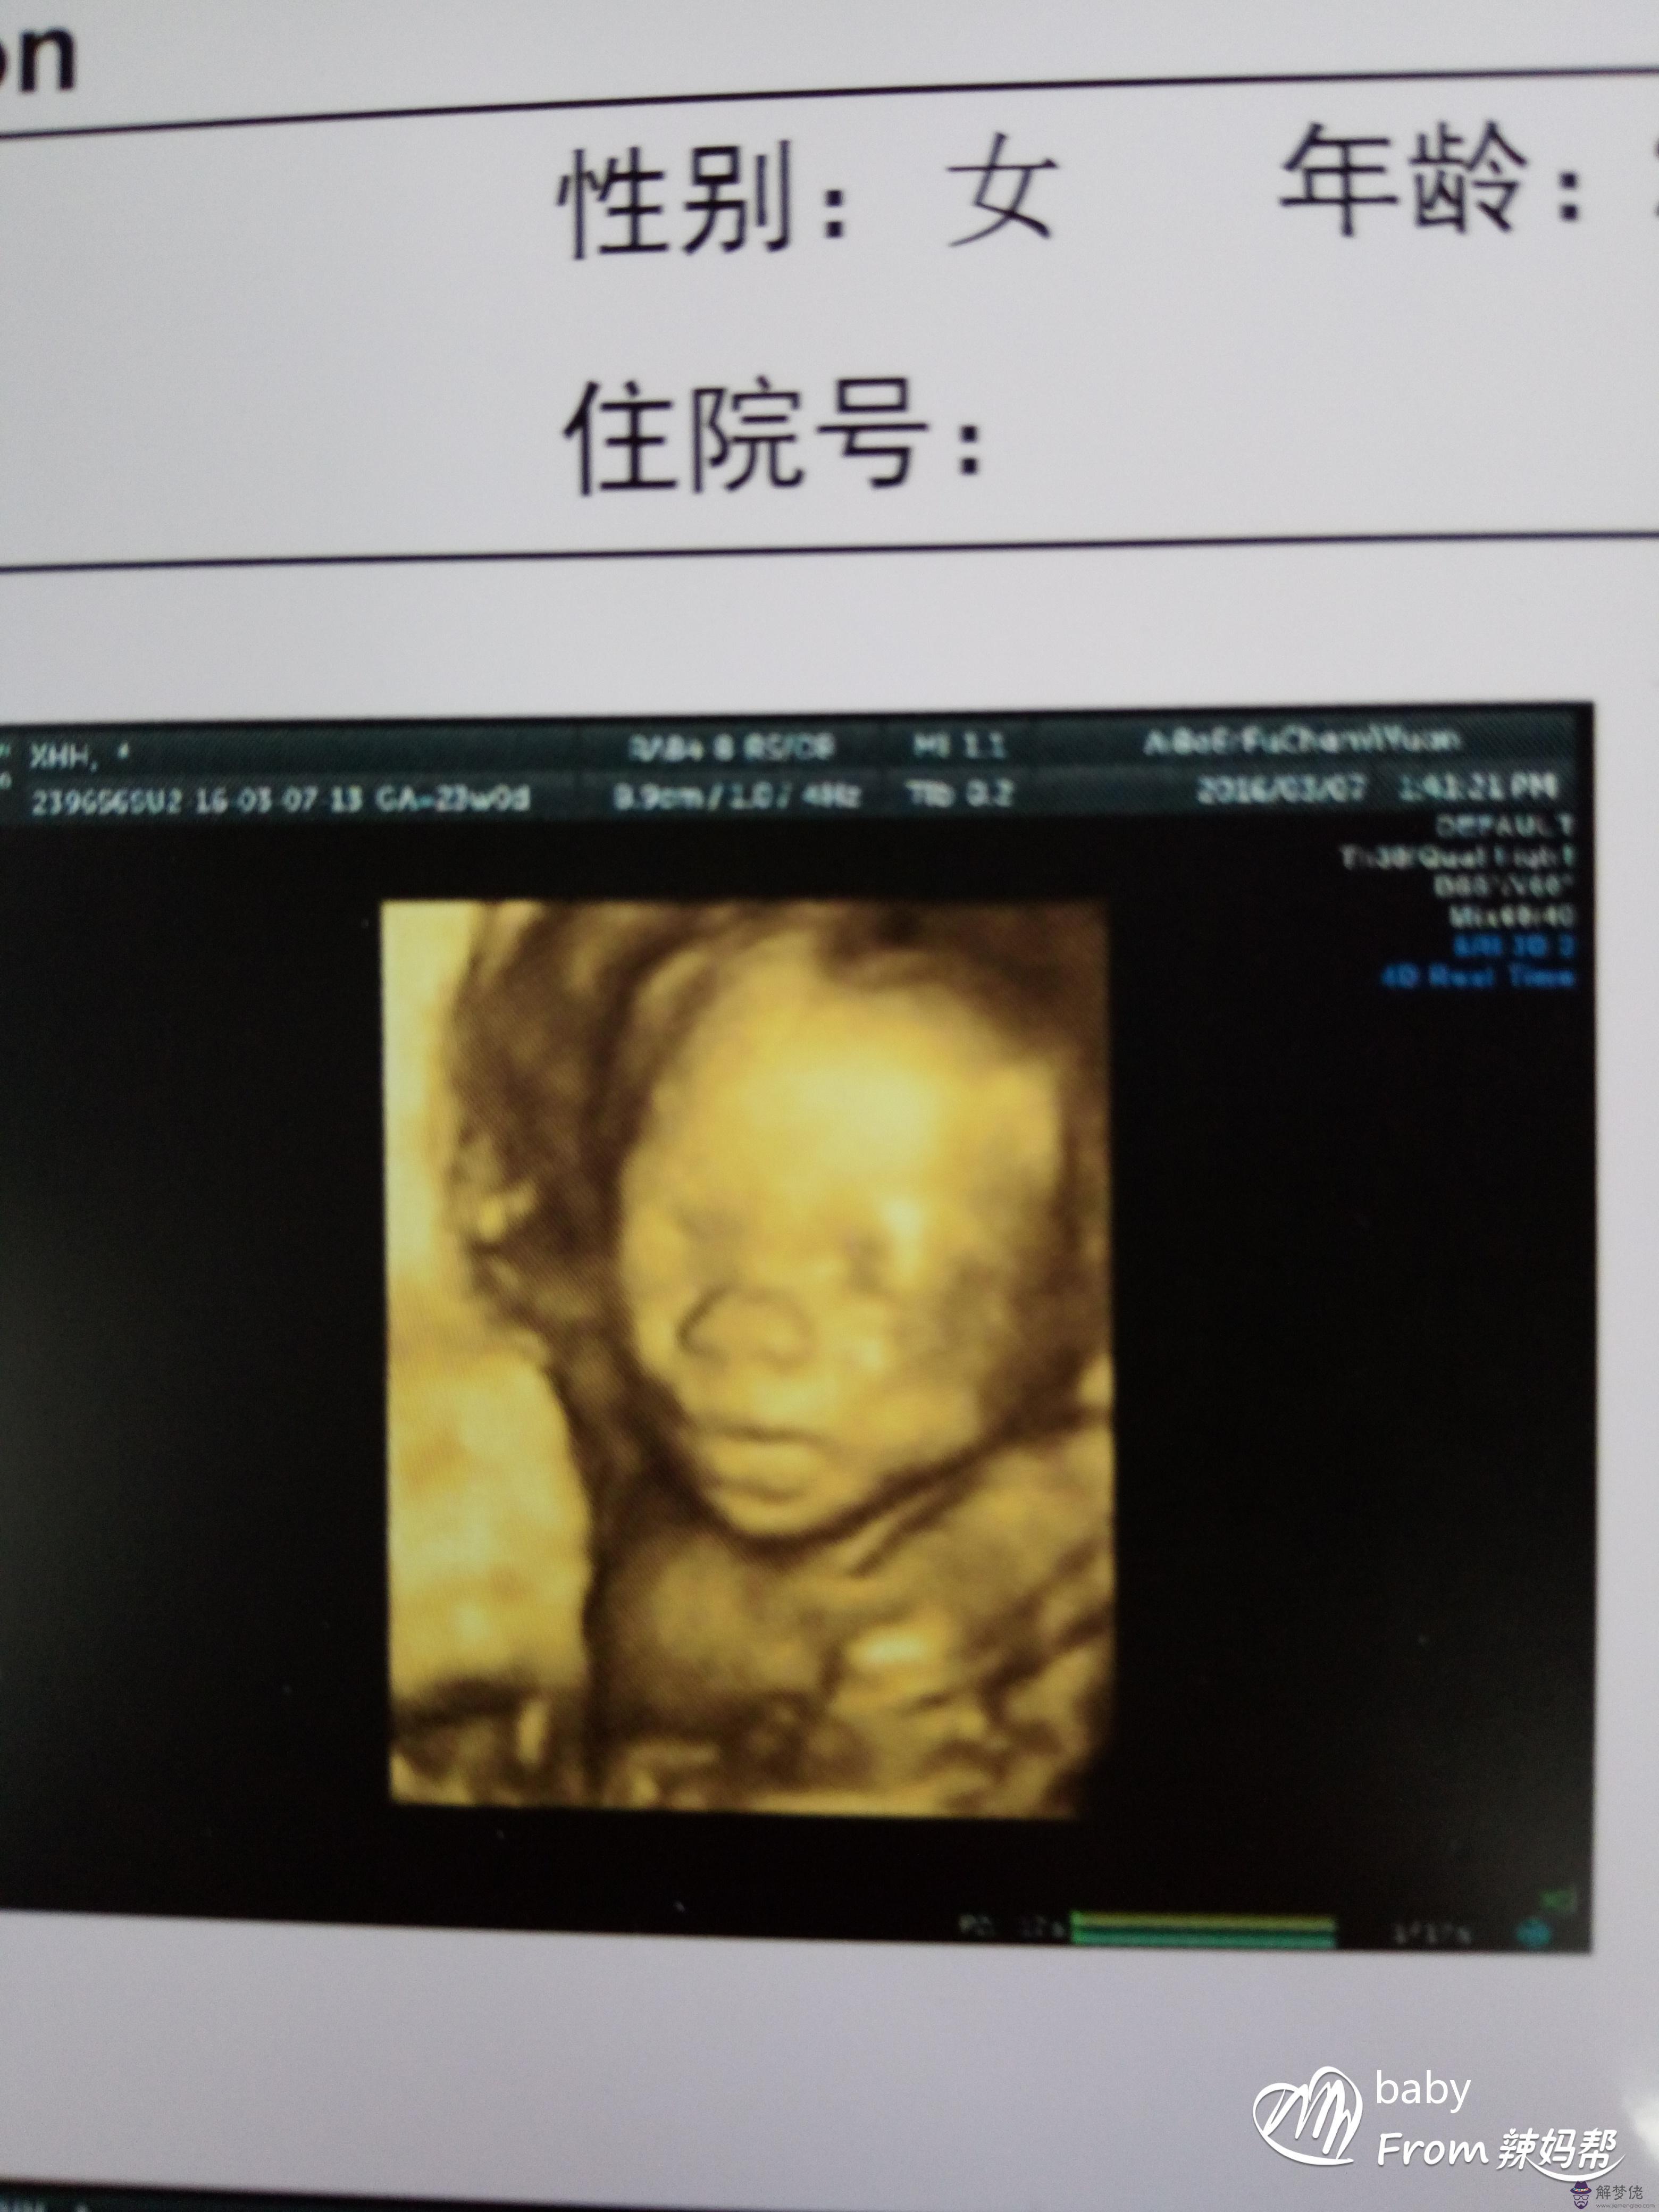

八、在孕期照B超的時候顯示胎兒臉朝外的為男;面對媽咪的則為女。